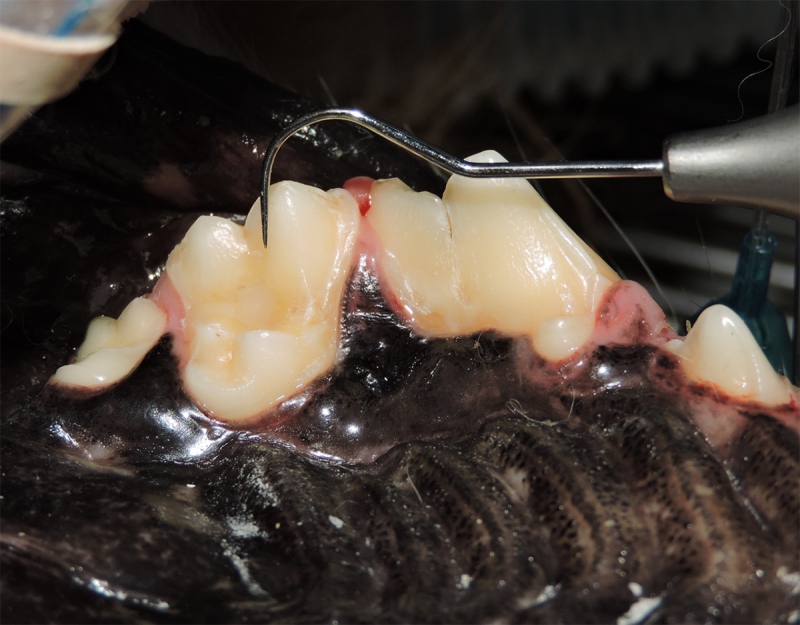

Tumors of the Maxilla, Mandible and Facial Area

Oral tumors are very common in dogs and cats. Many of these tumors can be successfully removed with surgery. Benign tumors can be cured with surgery alone, and malignant tumors can be treated with surgery and some combination of radiation or chemotherapy. In many cases oral tumors cause a great degree of discomfort or are bleeding and need to be removed to allow your pet to be more comfortable.